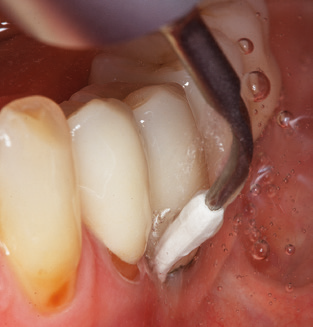

Die gute Ausleuchtung des Arbeitsfeldes stellt eine wesentliche Erleichterung dar. Bei dem von den Autoren genutzten System ist dies gelungen, indem ein 5­facher LED­Ring in das Handstück integriert wurde. Natürlich werden für dieses System unterschiedliche Arbeitsspitzen für die jeweiligen Indikationsbereiche angeboten. Eine gerade, universell einsetzbare Spitze ist das Basisinstrument zur maschinellen Instrumentierung natürlicher Zähne (Abb. 5a und b). Für schwer zugängliche Bereiche im Seitenzahnbereich werden gebogene Spitzen angeboten, die auch einen Zugang zu freiliegenden Furkationen ermöglichen (Abb. 6).

Abb. 4: Für das Sondieren an dentalen Implantaten sind biegsame, millimeterskalierte Sonden empfehlenswert (z.B. Colorvue Kit PCV11KIT6, Hu-Friedy). – Abb. 5a und b: Eine gerade Arbeitsspitze (1P, W&H Dentalwerk Bürmoos GmbH) ist universell für die Instrumentierung natürlicher Zähne geeignet. – Abb. 6: Für die Bearbeitung schwer zugänglicher Bereiche der Zahn- und Wurzeloberflächen (z.B. Furkationen) bieten sich gebogene Arbeitsspitzen (3Pr/3Pl, W&H Dentalwerk Bürmoos GmbH) an. – Abb. 7: Die spitz zulaufende sechseckige Implantatreinigungsspitze (1I, W&H Dentalwerk Bürmoos GmbH) ermöglicht eine atraumatische und effiziente Reinigung der Kronen- und Abutmentoberflächen. – Abb. 8: Für die manuelle Instrumentierung der Implantatoberflächen sind Titan- oder Carbonküretten geeignet.